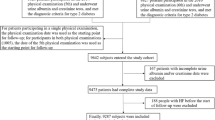

Being a prospective cohort study, health examinations for active and retired Kailuan Group personnel were conducted every two years from June 2006 to October 2007 in 11 hospitals, including Kailuan General Hospital and its affiliated hospitals. Follow-up assessments included incident HF and mortality. In the 6th health examination in 2016, cystatin C was investigated in T2D patients. We selected T2D patients who participated in this health examination and underwent cystatin C investigations as our study subjects. The inclusion criteria were: (1) Those who participated in the 2016 annual health examination and met the diagnostic criteria for T2D; (2) Patients with the availability of primary research data, including cystatin C and serum creatinine, and (3) Those willing to participate and provide informed consent. The exclusion criteria were: (1) Patients with a history of HF before the health examination and (2) Those having valvular and congenital heart diseases, respectively.

We included 7,967 participants who met the diagnostic criteria for T2D and underwent the 6th health examination as well as cystatin C and serum creatinine investigations.

More than half of participants had a baseline eGFRdiff between − 15 and 15 mL/min/1.73 m2 (4679 participants [58.7%]; midrange eGFRdiff); 2280 participants (28.6%) had an eGFRdiff less than − 15 mL/min/1.73 m2 (negative eGFRdiff ), and 1008 participants (12.6%) had an eGFRdiff of 15 mL/min/1.73 m2 or greater (positive eGFRdiff). Compared with the other 2 eGFRdiff groups, participants in the negative eGFRdiff group were older, more often female, with higher baseline SBP, BMI, uACR and more anti-diabetic and antihypertensive treatment (Table 1; Fig. 1).